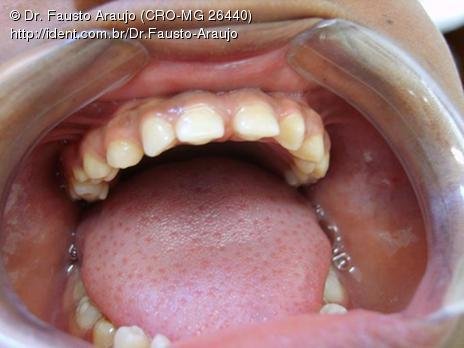

Paciente de 18 anos, negra com baixa estatura e aspecto sindrômico procura atendimento no Centro especializado médico odontológico do Municipio de Cristália - MG.

No Exame clínico foi observado diversos elementos apresetando microdontia e uma discreta macroglossia.

Fotos do caso